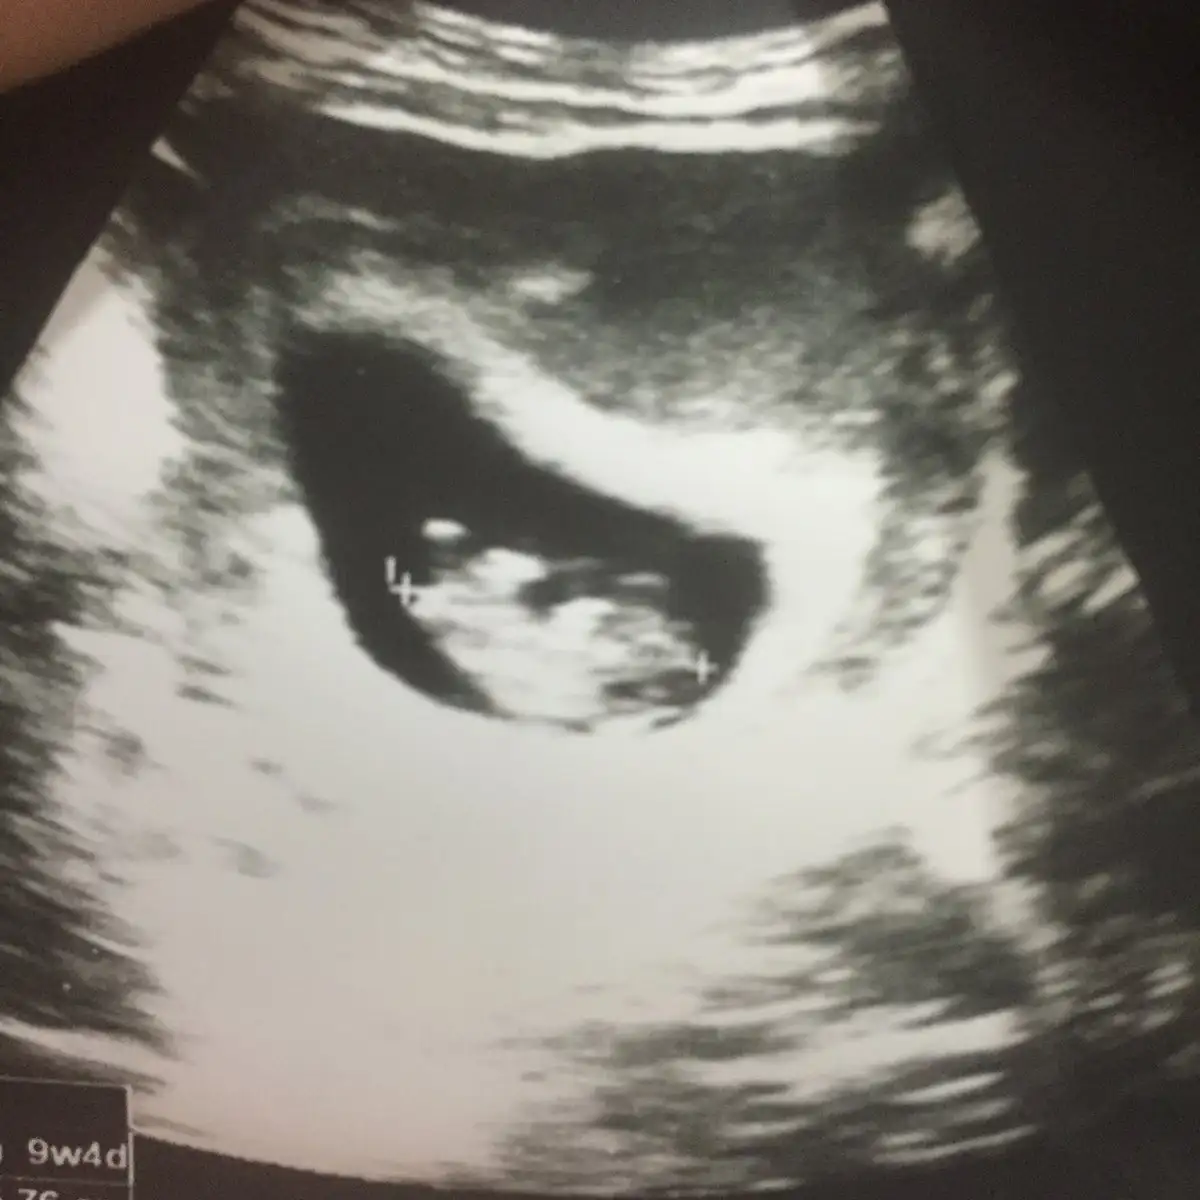

9+4 göre erken sekil almış erkek diyorumBende yorum alabilir miyimEki Görüntüle 2218569

Kız benceEki Görüntüle 2277369 Acaba benim bebişimin Cinsiyeti ne olabilir 8 haftalık Karından

Evet canım sağda duruyor teoriye göre öyleBu teoriye göre bizim kızmı oluyo şimdi arkadaslarkarında usg ile bakıldı